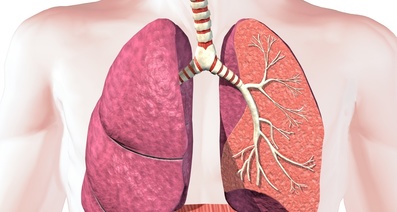

鼻や口から吸い込まれた空気は、気道を通り左右の肺に送られます。肺の内部には気管支があり、気管支が枝分かれを繰り返した先には「肺胞」と呼ばれる小さな袋状の組織が集まっています。この肺胞が機能しているおかげで、私たちはスムーズに呼吸することができます。

しかし、肺気腫になると、肺胞の壁が壊れてしまうことで隣の肺胞と合わさり、大きな袋のようになってしまうのです。大きな袋のようになった部分は伸びきった風船のようになり、弾力性がなくなります。その結果、呼吸機能が低下し、息切れなどの症状が現れるようになります。